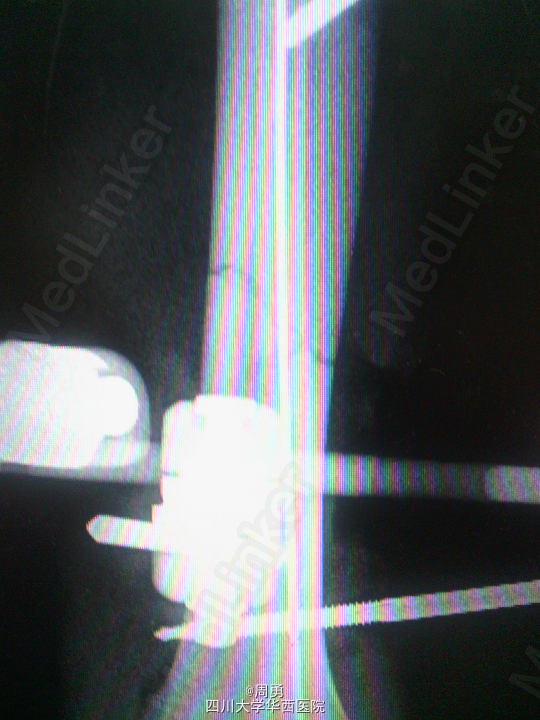

闭合穿针复位腓骨在开放性骨折中应用和意义

某些腓骨骨折常无需处理,但在开放性骨折一期处理创面同时,为了达到恢复肢体长度、条件允许情况下最大可能复位骨折、简化二期手术目的,某些时候复位腓骨并闭合穿克氏针对骨折复位和固定会有一定帮助,选几年前2个博士住院总期间X片示意,欢迎大家交流。